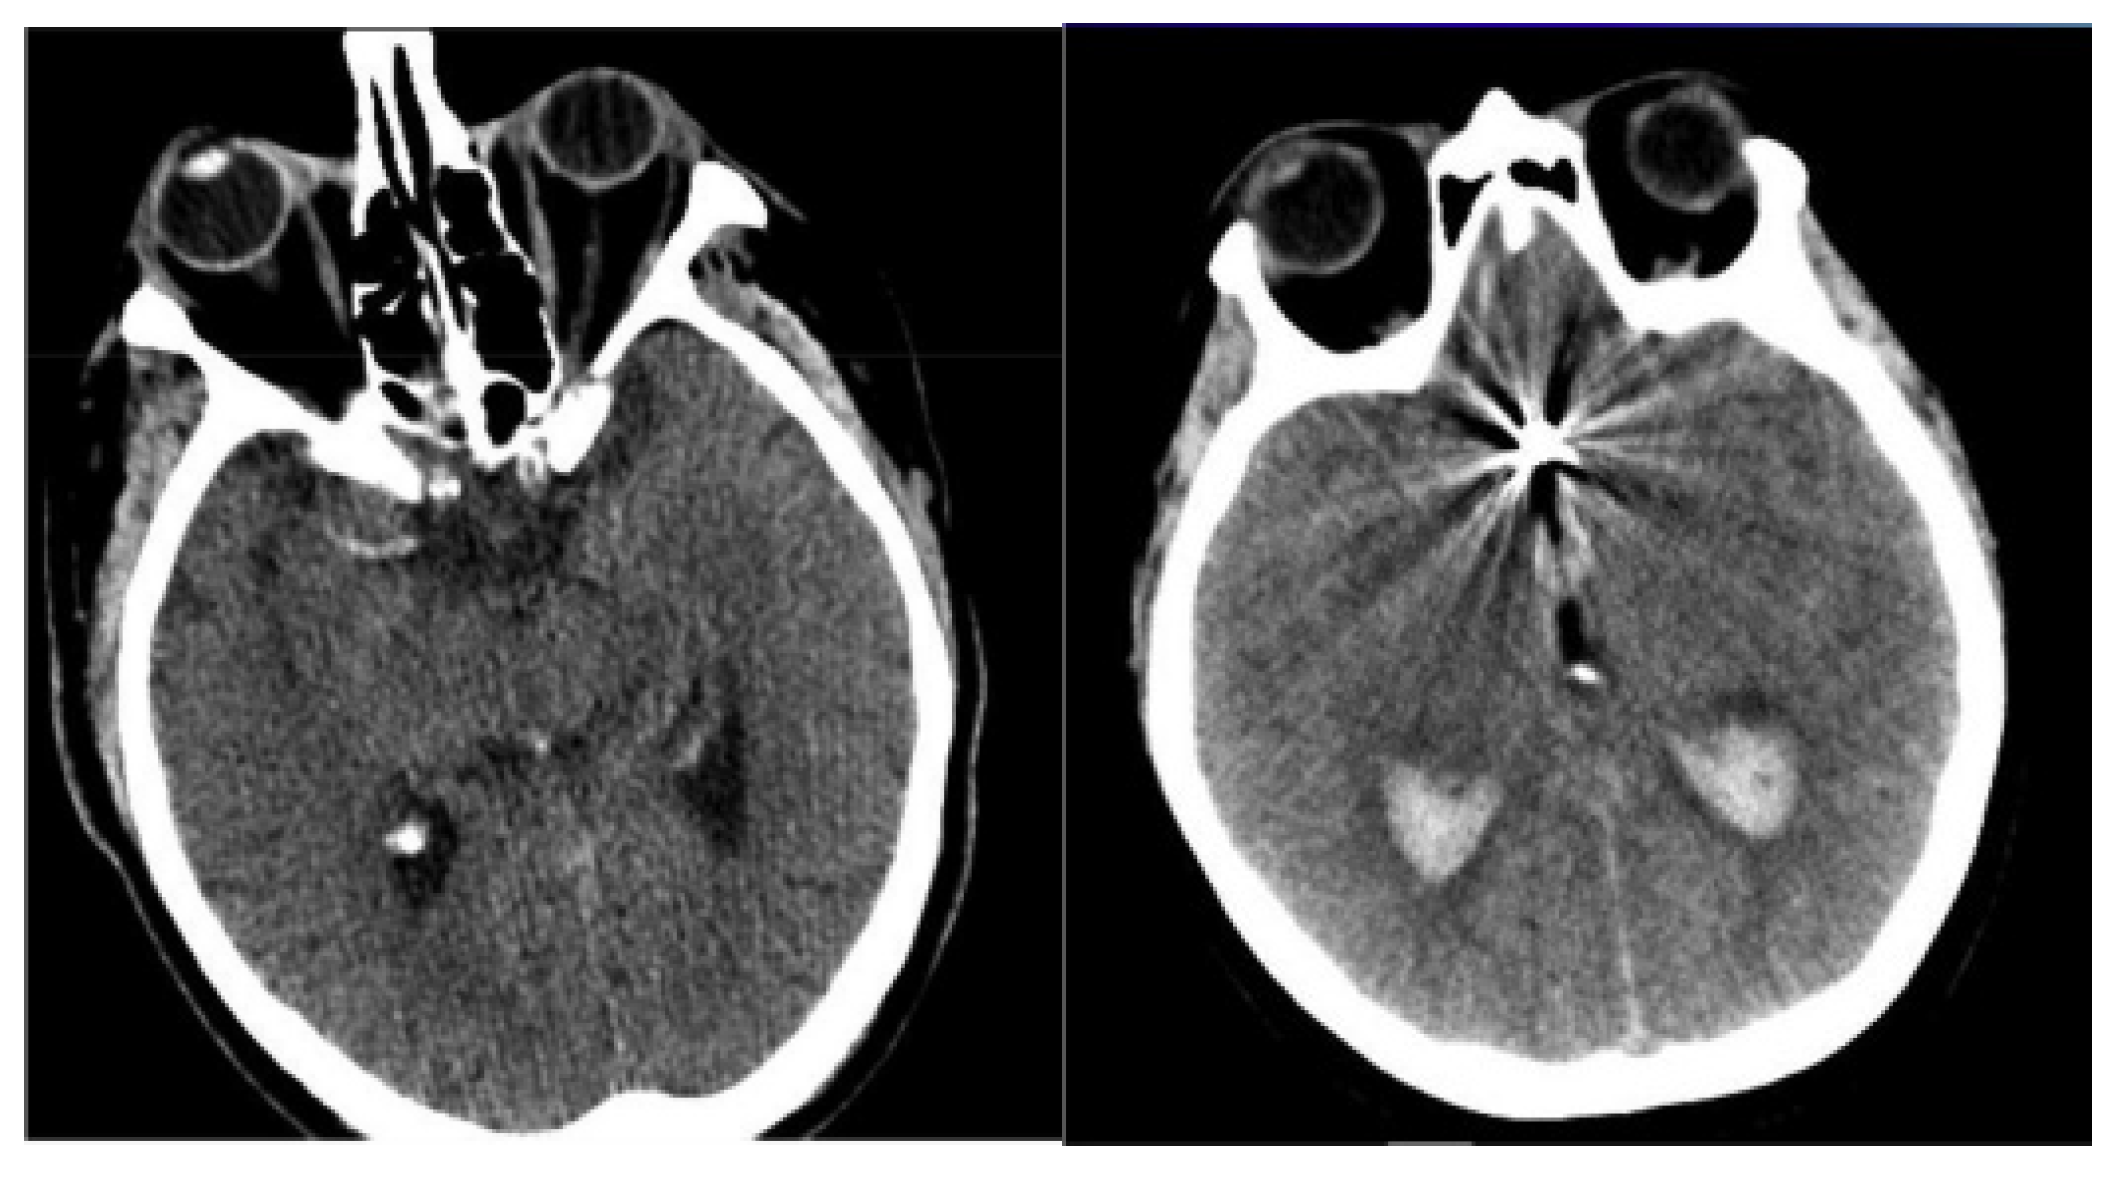

The NCCT brain images of 49 SAH patients were acquired from two distinct university hospitals in Lithuania. Patient inclusion criteria were: older than 18 years, diagnosed cerebral aneurysm rupture, initial NCCT scans performed routinely at patient admission. In order to increase the sample size, the collected NCCT brain images are augmented and can be used to mark regions of interest, specifically highlighting areas indicative of SAH. The image augmentation was performed by employing flipping, shifting, and random rotation techniques to generate more training images, as performing calculations with limited data samples in the deep learning models leads to overfitting problems. The use of image augmentation techniques reduces data overfitting, prevents data scarcity, and improves the model’s efficiency in image segmentation and classification. In total, 1400 NCCT images were generated, of which 1120 images were used in a training set, and the remaining 280 images were used in a testing set. The sample-acquired NCCT images are given in Figure 2.

Figure 2.

Sample-acquired NCCT images.